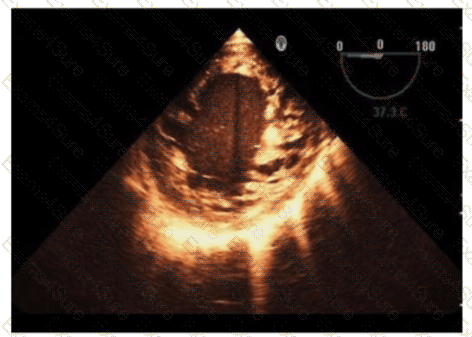

Which is the most likely abnormality represented in these images from a 48-year-old man with shortness of breath?